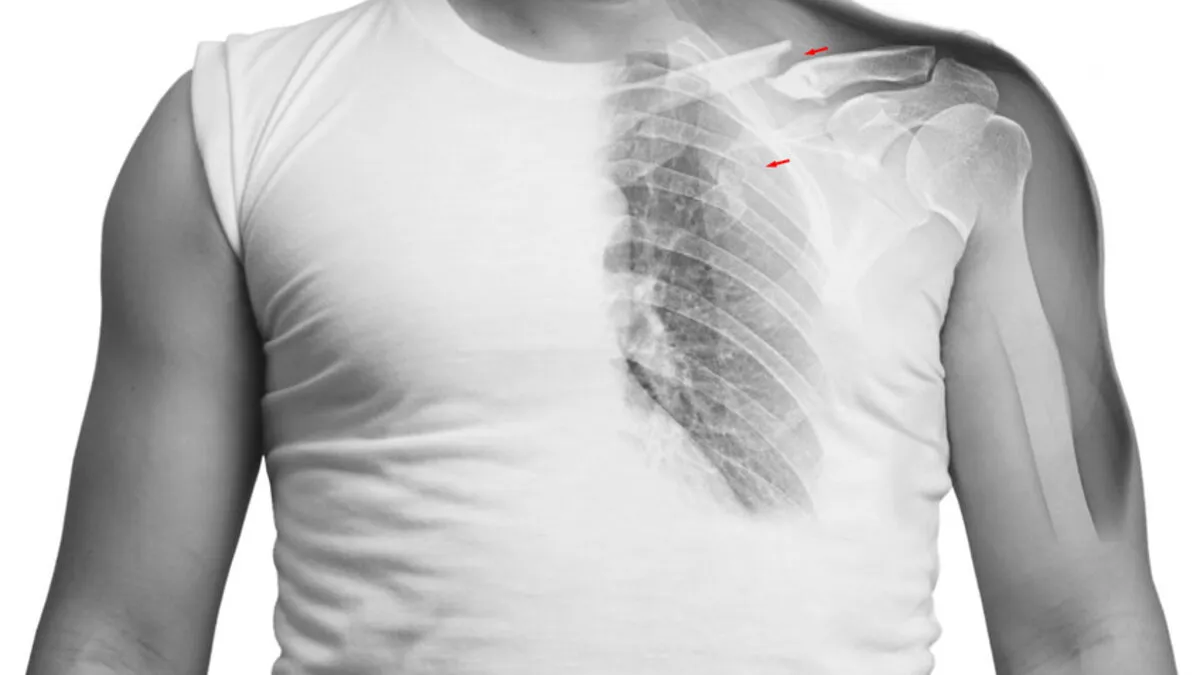

- RTG klatki piersiowej: To podstawowe badanie, które pozwala wykluczyć złamanie żebra, odmę opłucnową (obecność powietrza w jamie opłucnej) czy inne poważne zmiany w płucach. Jest szybkie i łatwo dostępne.